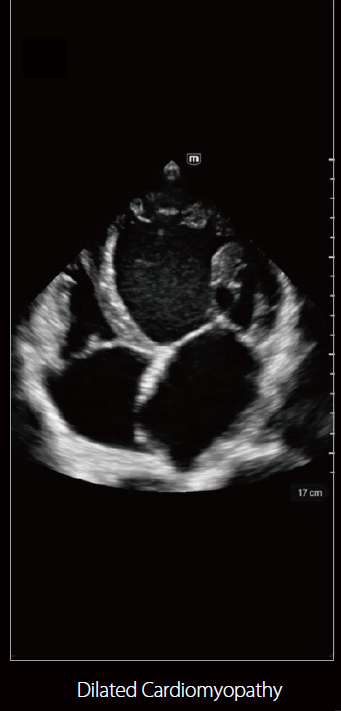

صور متعلقة